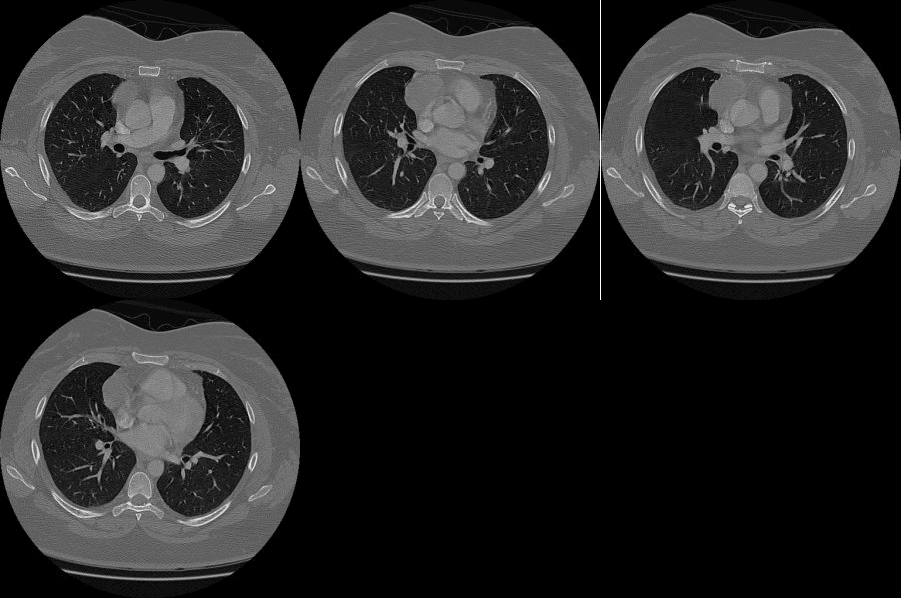

Subsequent CT shows an anterior mediastinal mass most consistent with a thymoma.